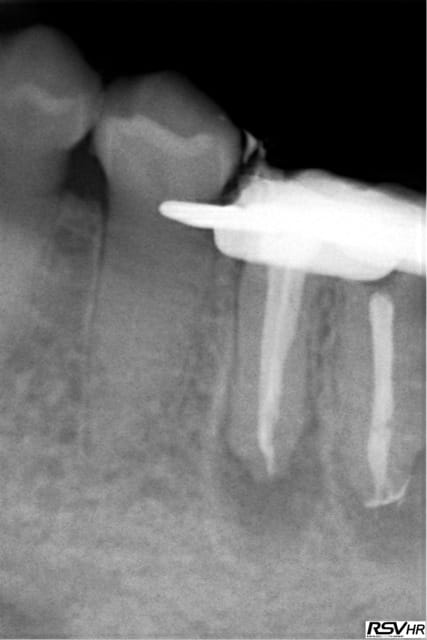

Voici un exemple de couplage microscope opératoire/cbct

RTE 36 en octobre2012 ;3 heures de RTE pour recherche de canaux sous micro inserts ultrasons/il y avait une LIPOE

digue+hypo+système R-endo microméga instruments à mains

vérification au CBCT en 2016

disparition des LIPOE

ici on obtient une guérison apicale